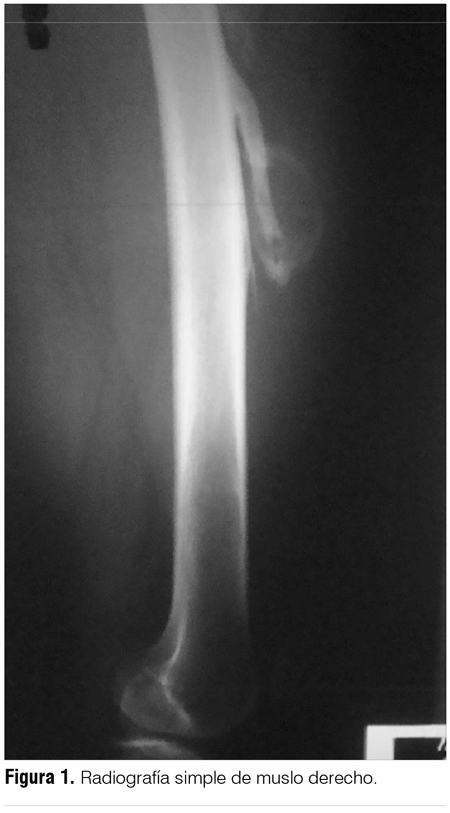

En la radiografía simple de muslo se observa a nivel de tercio medio una imagen inespecífica adyacente al fémur, visualizándose además una neoformación ósea perpendicular al mismo (figura 1).